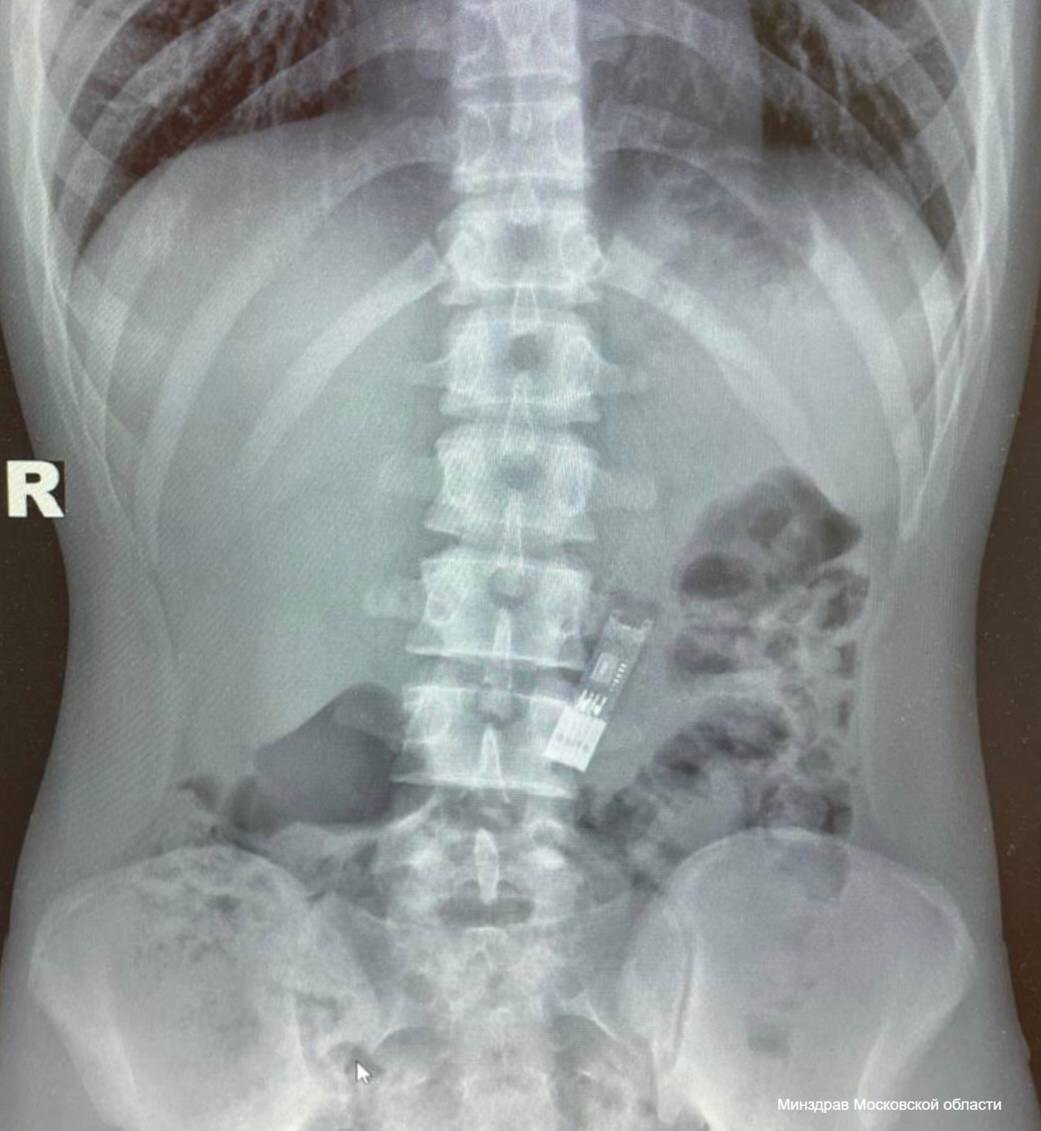

В Подмосковье школьник проглотил флешку с домашним заданием по информатике

По словам подростка, это произошло случайно - он решил поиграть с ней, крутил перед лицом, а потом каким-то образом проглотил. 16-летнего пострадавшего доставили в центр Рошаля, где с помощью специальных щипцов врачи извлекли карту памяти без единого разреза. Флешка не успела навредить его организму и сохранила работоспособность, сообщили в Минздраве Московской области. Домашнюю работу подростка успешно приняли в школе.